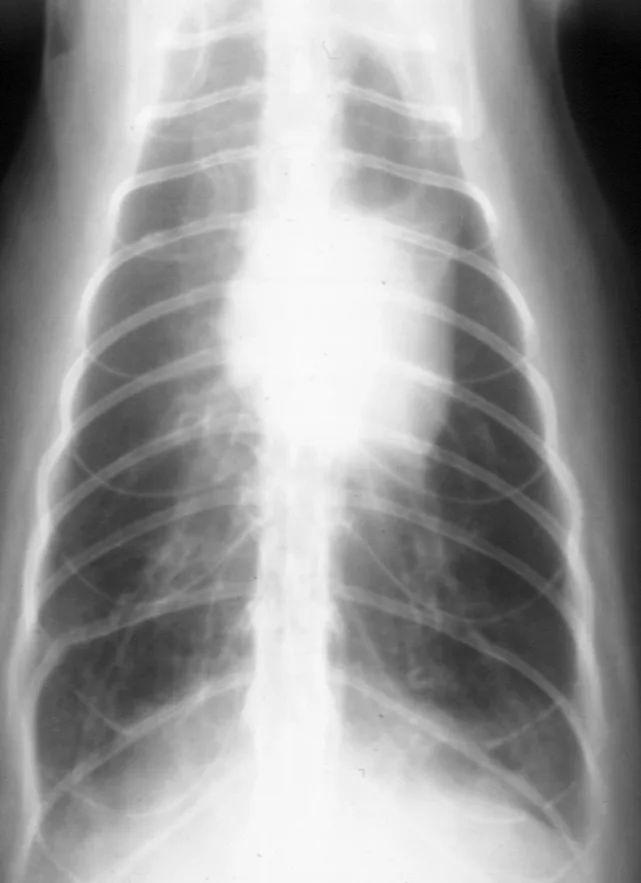

• When lower airway tract disease is suspected, good-quality thoracic radiography is essential. Both lateral views and a ventrodorsal (or dorsoventral) view should be obtained. Radiography can confirm and localize disease and also provide information on severity of changes.

• Radiographic changes in "asthmatic" cats often include a prominent bronchial pattern (tram lines and donuts) or a mixed pattern of bronchial, alveolar, or interstitial changes. With increasing disease severity or chronicity, atelectasisof the right middle lung lobe or left cranial lobe (caudal segment) and generalized lung overinflation may be evident (Figure 3).

Featured Image

FIGURE 3 Thoracic radiograph of a cat with long-standing disease. A prominent bronchial pattern, general hyperinflation, and atelectasis of the left cranial lobe (caudal segment) are evident.